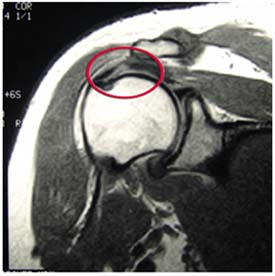

An MRI can sometimes tell how large the tear is, as well as its location within the tendon itself or where the tendon attaches to bone.

Magnetic resonance image shows a

full-thickness rotator cuff tear within the tendon.